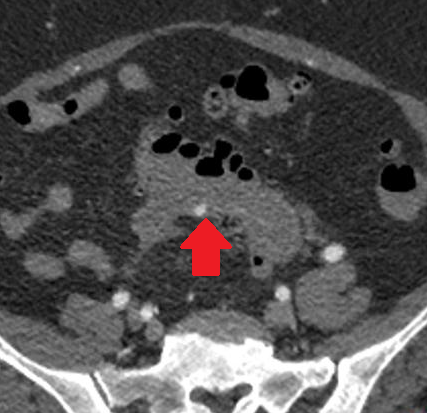

Σχήμα 5 . Η αξονική τομογραφία έδειξε μια οπισθοπεριτοναϊκή μάζα που περιβάλλει τον αριστερό οσφυϊκό ουρητήρα και προκαλεί ουρητηρο-υδρονέφρωση: Η βλάβη αυτή υποδηλώνει υποτροπή . ( Ευγενική παραχώρηση Δρ. Β. Πενόπουλος ) .